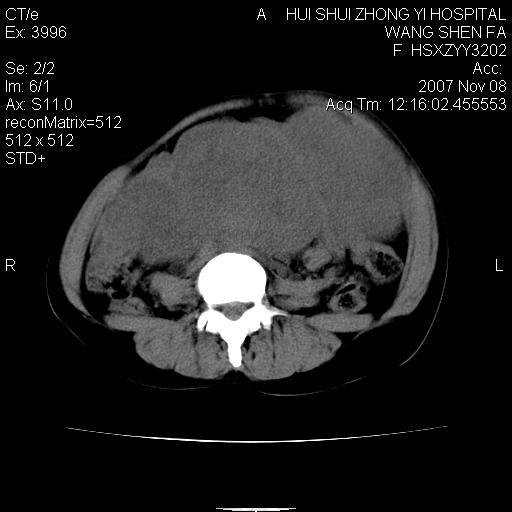

标题: CT10389:女,38岁,腹部巨大包块 [打印本页]

标题: CT10389:女,38岁,腹部巨大包块

腹部巨大包块半年,质硬,边界不清。

腹腔及盆腔内可见巨大软组织肿物影,内部密度欠均匀,边界尚清晰,周围组织受压移位明显,右侧输尿管受压明显,上端扩张肾盂轻度积水,病灶外形分叶明显,似多个肿物融合而成。考虑来源于间叶组织的恶性肿瘤可能性大

下腹部巨大软组织影,密度不均匀,并可见分隔,病灶边缘较清,肠管受压移位。子宫未显示。盆腔、双侧腹股沟未见明显肿大淋巴结。考虑:1.卵巢病变可能性大,囊腺癌>卵巢癌>囊腺瘤.2.多发性阔韧带子宫肌瘤待除外.

腹腔及盆腔内可见巨大软组织肿物影,内部密度欠均匀,边界尚清晰,周围组织受压移位明显,膀胱前上移位,右侧输尿管受压明显,上端扩张肾盂轻度积水。考虑:1卵巢病变可能性大,囊腺癌>卵巢癌>囊腺瘤.2 子宫病变,子宫肌瘤?